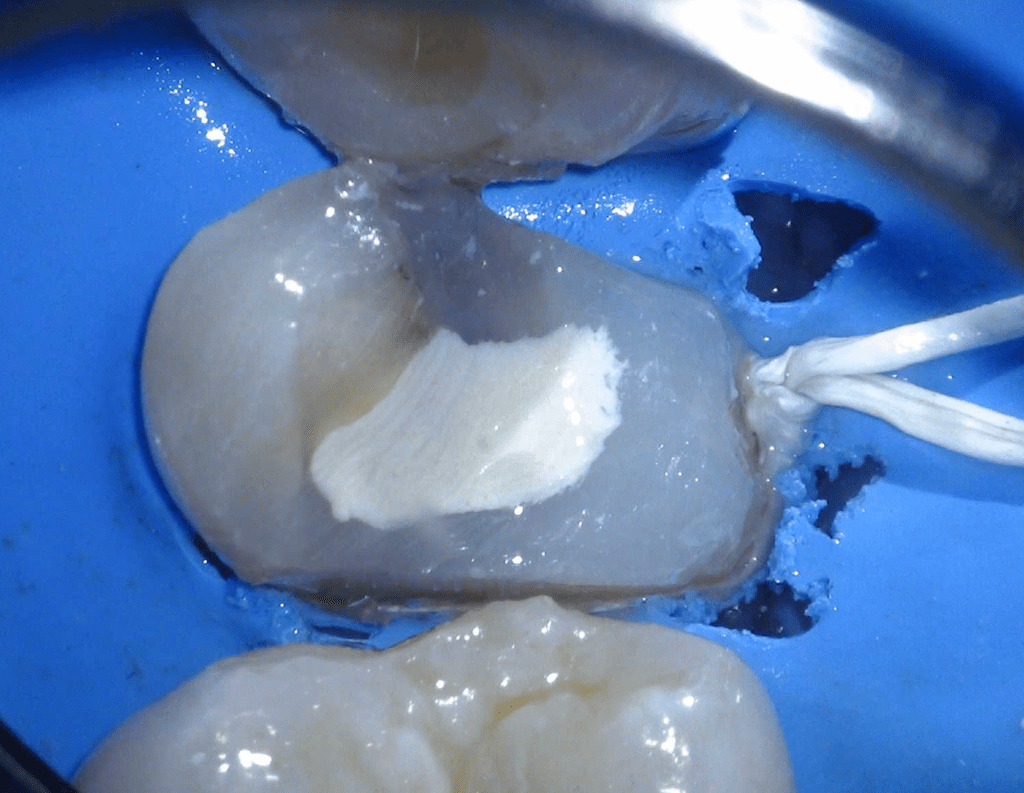

Pulpotomía biodentine + reco preendio